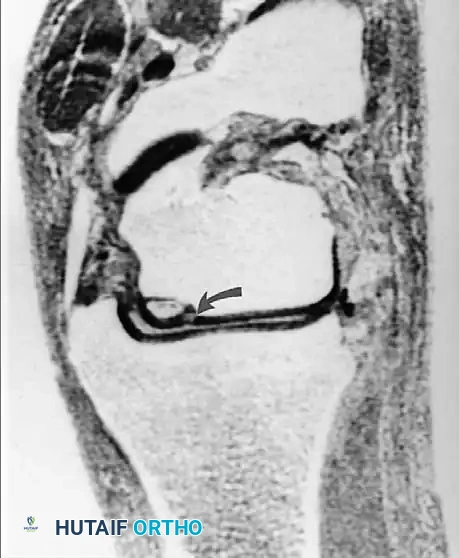

تقييم الغضاريف الهلالية

تتسبب الحالات المرضية للغضروف الهلالي في نسبة كبيرة من آلام الركبة والإعاقة الحركية. تظهر الغضاريف الهلالية الطبيعية في الرنين المغناطيسي كأشكال مثلثة داكنة اللون. عندما يحدث تغير في هذا اللون الداكن وتظهر إشارات مضيئة داخله، يصنف أطباء الأشعة هذه التغيرات إلى ثلاث درجات:

- الدرجة الأولى: مناطق دائرية من الإشارة المتزايدة داخل الغضروف.

- الدرجة الثانية: مناطق خطية من الإشارة المتزايدة لا تصل إلى السطح.

- الدرجة الثالثة: خط غير طبيعي يمتد ليصل إلى السطح المفصلي العلوي أو السفلي.

من المهم جدا للمرضى أن يعرفوا أن الدرجة الأولى والثانية لا تمثل تمزقا حقيقيا، بل هي مجرد تغيرات تنكسية طبيعية لا تحتاج لتدخل جراحي. فقط الدرجة الثالثة هي التي تعبر عن تمزق حقيقي في الغضروف.

يجب تحديد التمزق بدقة من حيث موقعه وشكله سواء كان أفقيا، عموديا، معقدا، أو شعاعيا.

التمزقات المعقدة والمزاحة

بعض التمزقات تكون شديدة لدرجة أن جزءا من الغضروف ينفصل وينزاح من مكانه الأصلي ليستقر في منتصف المفصل، مثل تمزق يد الدلو، مما يسبب انغلاق الركبة الميكانيكي.